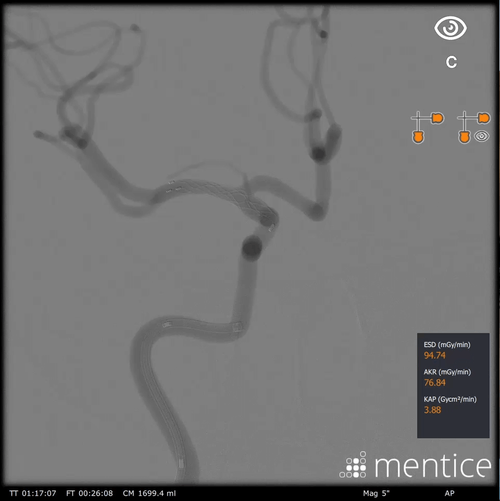

Hands-on training for image-guided interventional treatment of intracranial artery stenosis (ICAD)

The ICAD cases teach specific skills for treating intracranial artery stenosis, focusing on the basic steps of assessing the severity of the stenosis, choosing the proper material, navigating to and crossing the stenosis, and treating the stenosis using balloon dilatation and stenting.

Assess the size and morphology of the stenosis, as well as the tortuosities of the access path, using angiograms and 3DRA

Treat the stenosis using angioplasty and stenting